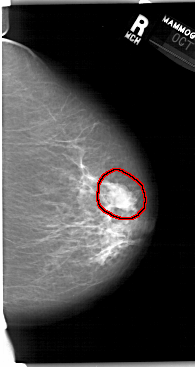

A_1411_1.RIGHT_CC

RIGHT_CC LINES 6601 PIXELS_PER_LINE 3496 BITS_PER_PIXEL 12 RESOLUTION 43.5 OVERLAY

FILE: A_1411_1.RIGHT_CC.OVERLAY

TOTAL_ABNORMALITIES 1

ABNORMALITY 1

LESION_TYPE MASS SHAPE LOBULATED MARGINS MICROLOBULATED

ASSESSMENT 4

SUBTLETY 4

PATHOLOGY BENIGN

TOTAL_OUTLINES 1

BOUNDARY